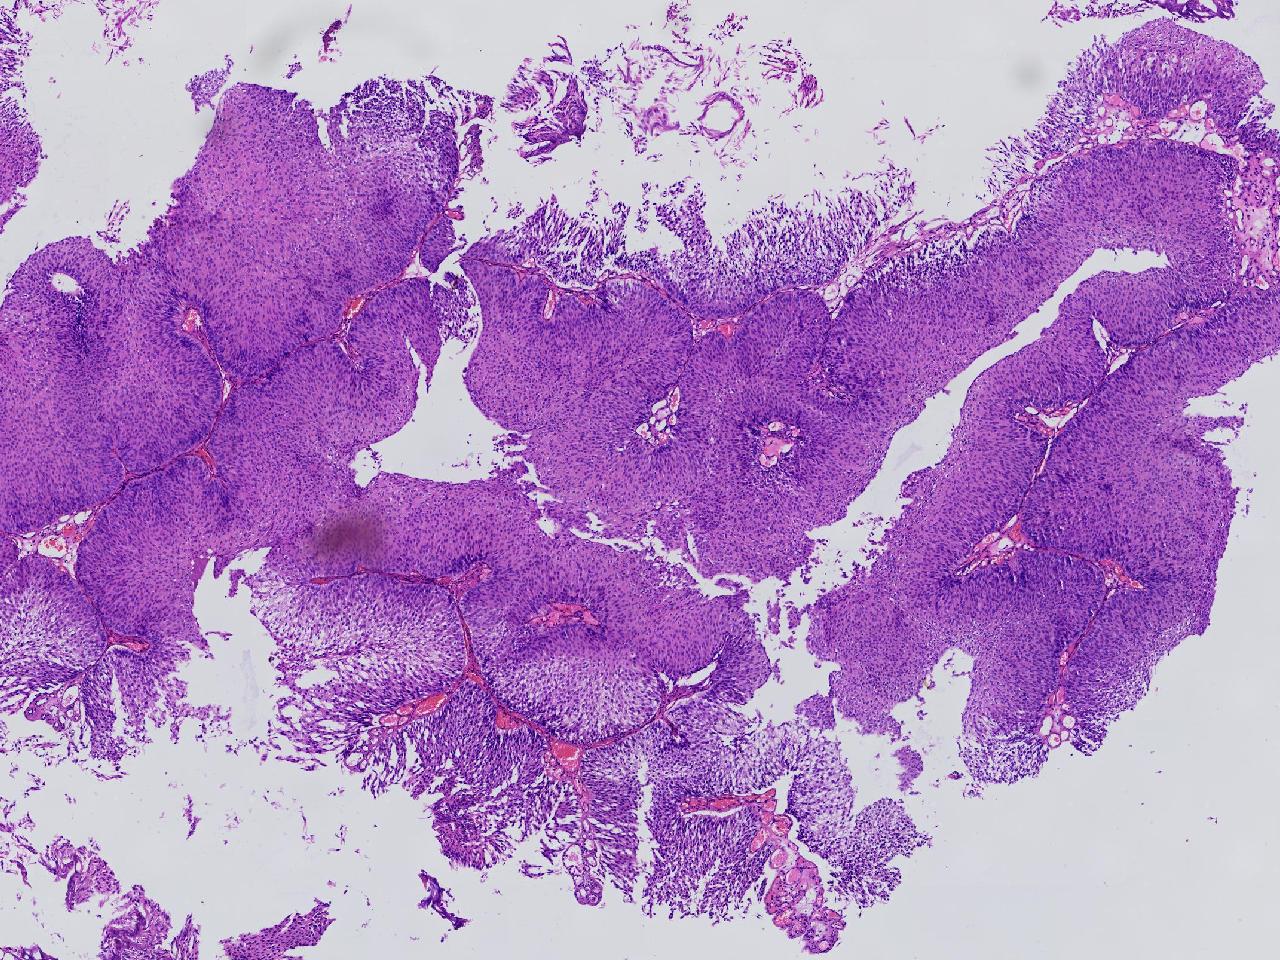

男,79岁,膀胱肿物。

膀胱肿物

灰白色不整形软组织多块,2X1X1厘米。

考虑:乳头状尿路上皮癌

考虑低级别,非浸润。

乳头状尿路上皮癌,低级别。

这几张图片上没有看到明确的浸润。